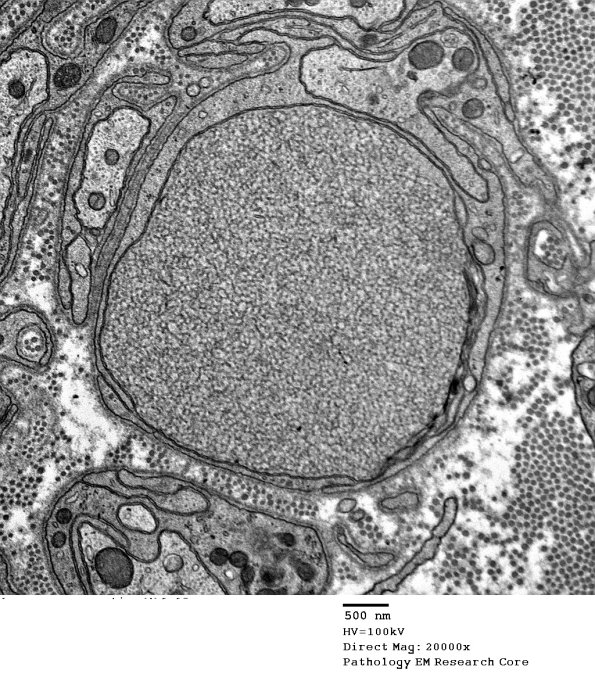

There were numerous dystrophic elements in this case. (electron micrographs)